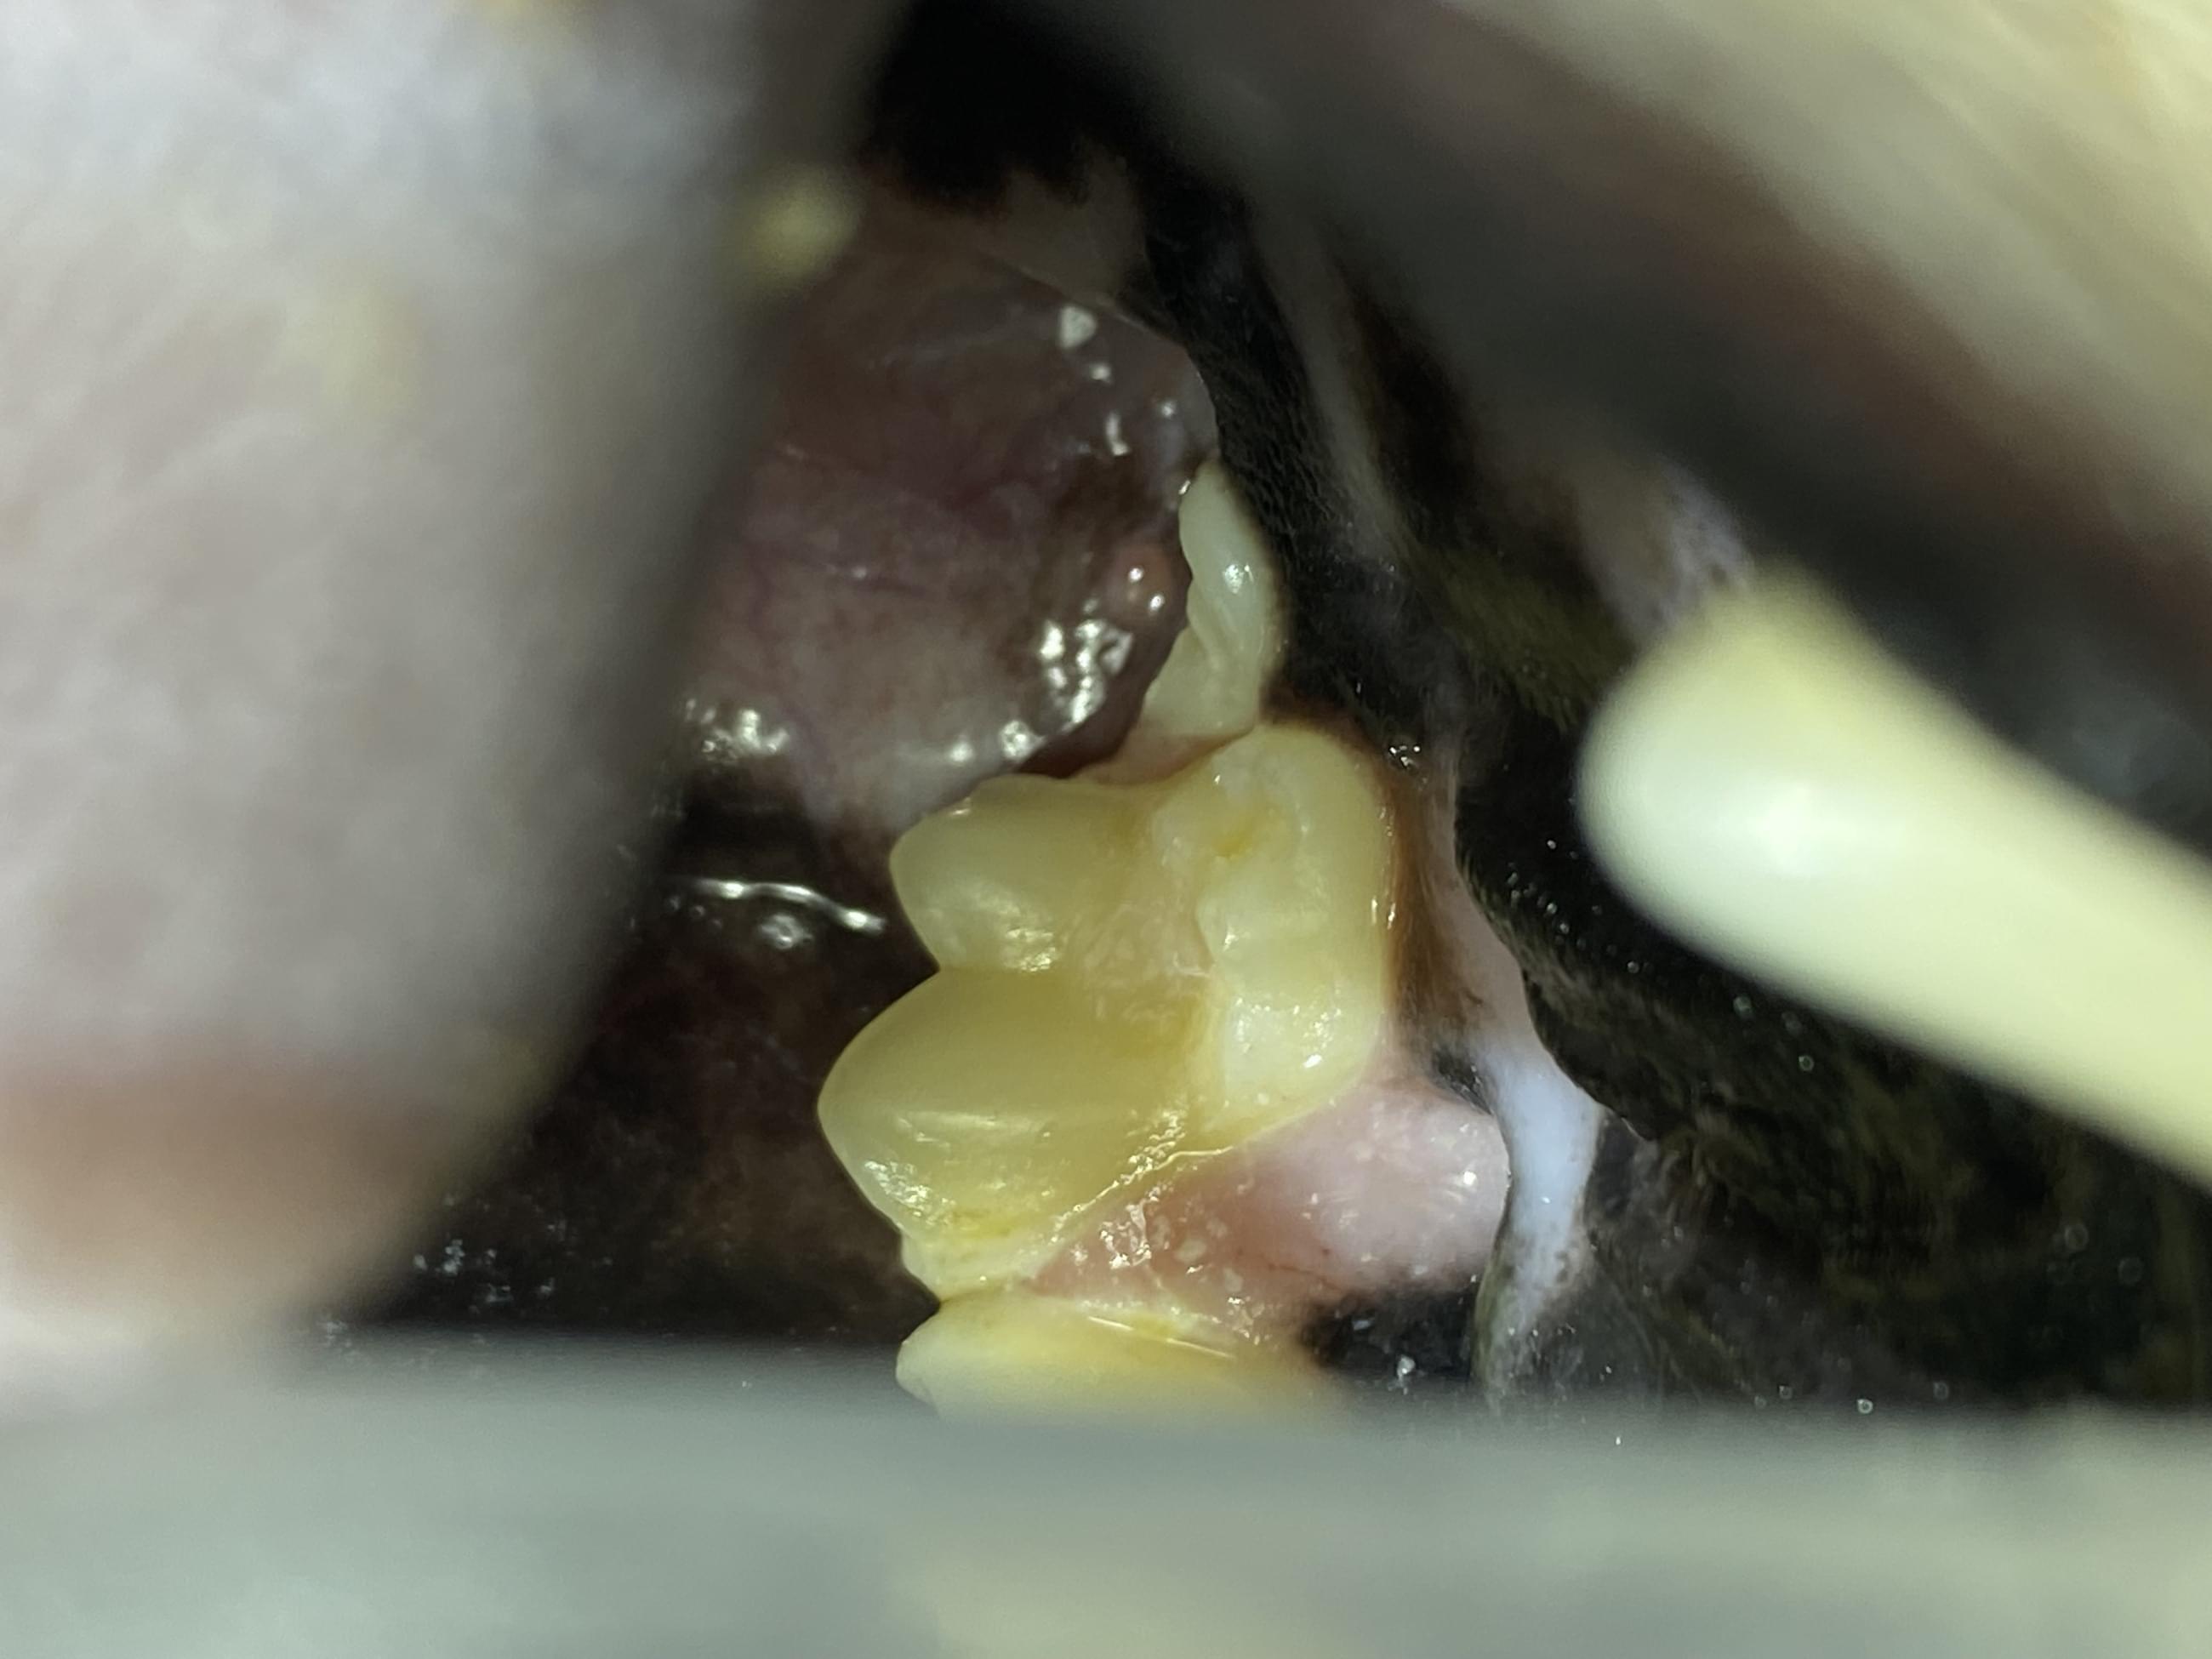

Počáteční lézí kazu je kyselá demineralizace skloviny. Toho je dosaženo kariogenními bakteriemi, které fermentují cukr, a tím uvolňují kyseliny na povrch zubu. U psů se kaz obvykle vyskytuje na okluzních plochách molárních zubů (těch velkých vzadu). Má vzhled hnědé až černé léze s měkkým povrchem.

Ošetření kazu probíhá prakticky totožně jako ošetření lidským stomatologem. Kazivá struktura zubu musí být odstraněna pomocí zubní frézy, dokud není dosaženo zdravého dentinu. Je třeba provést rentgenový snímek, aby se zjistilo, zda se infekce rozšířila do dřeně, v takovém případě zub také vyžaduje terapii kořenového kanálku. Chybějící struktura zubu je poté obnovena pomocí kompozitu. Psi, kteří měli zubní kaz, jsou náchylní k dalším lézím.